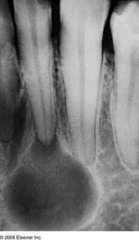

radicular cyst

-asymptomatic radiolucency associated with the root of a NONVITAL tooth